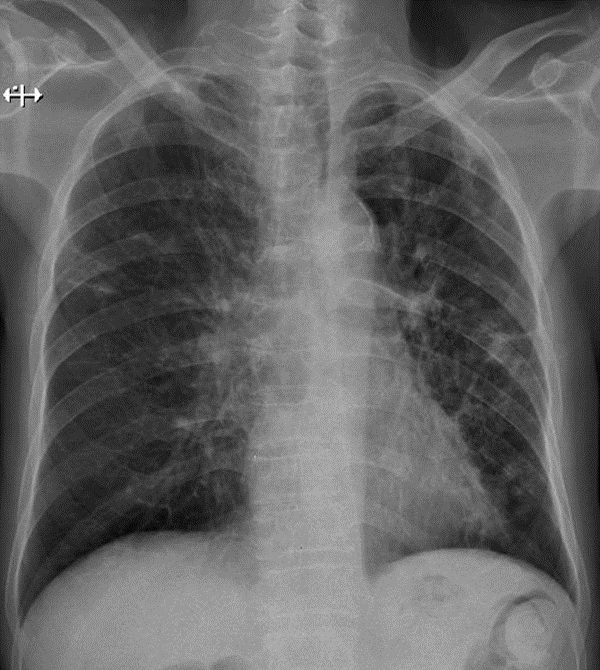

1-Khí quản bị chèn ép bên (P)-> U trung thất trước (Bướu giáp thòng thùy phải) 2-Xơ rải rác hai phổi 3-Dày dính màng phổi hai bên 4-Cung động mạch chủ đóng vôi